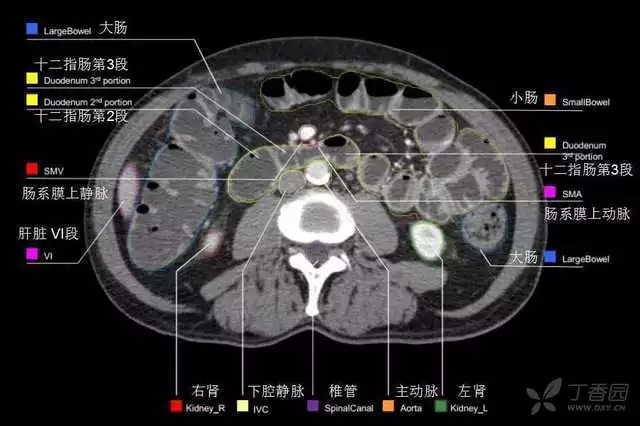

腹部肝脏高清CT断层的图谱

全腹部高清CT图谱,淋巴结彩色图谱,血管解剖图谱大汇总!

超声肝脏分叶及分段

肝脏分段和基本解剖学标志